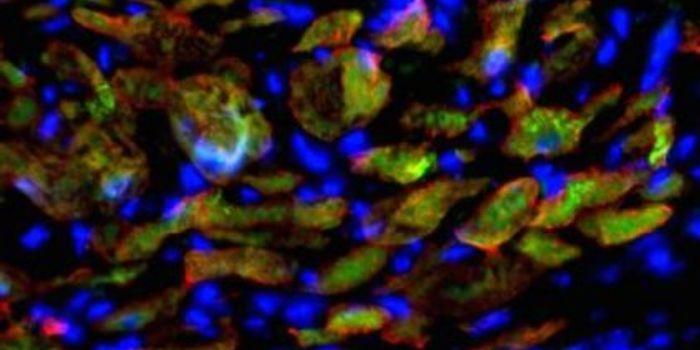

JUN 29, 2021ImmunologyResearchers at the Washington University School are getting to the root of heart damage resulting from COVID-19 infectio ...

JAN 20, 2022CardiologyNew research has shown changes to heart muscle tissue in patients who died of COVID-19.